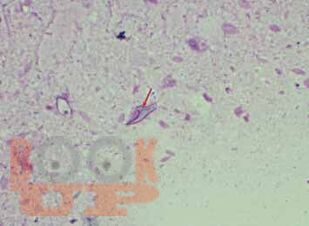

The book describes the general cytology, exfoliative cytology, laboratory techniques, and fine-needle aspiration cytology. The main asset of the book is the demonstration of different cytological techniques in a video format. A simple, concise, illustrative book with a large number of tables, boxes, line arts, and microphotographs. The molecular pathology and immunocytochemistry of various tumors are described. All the updated classification of the World Health Organization and International Academy of Cytologists are included. The digital pathology, whole-slide scanning and artificial neural network, polymerise chain reaction, and next-generation sequencing are described in detail. The significant addition of the book is the introduction of different cytological techniques in a video format.